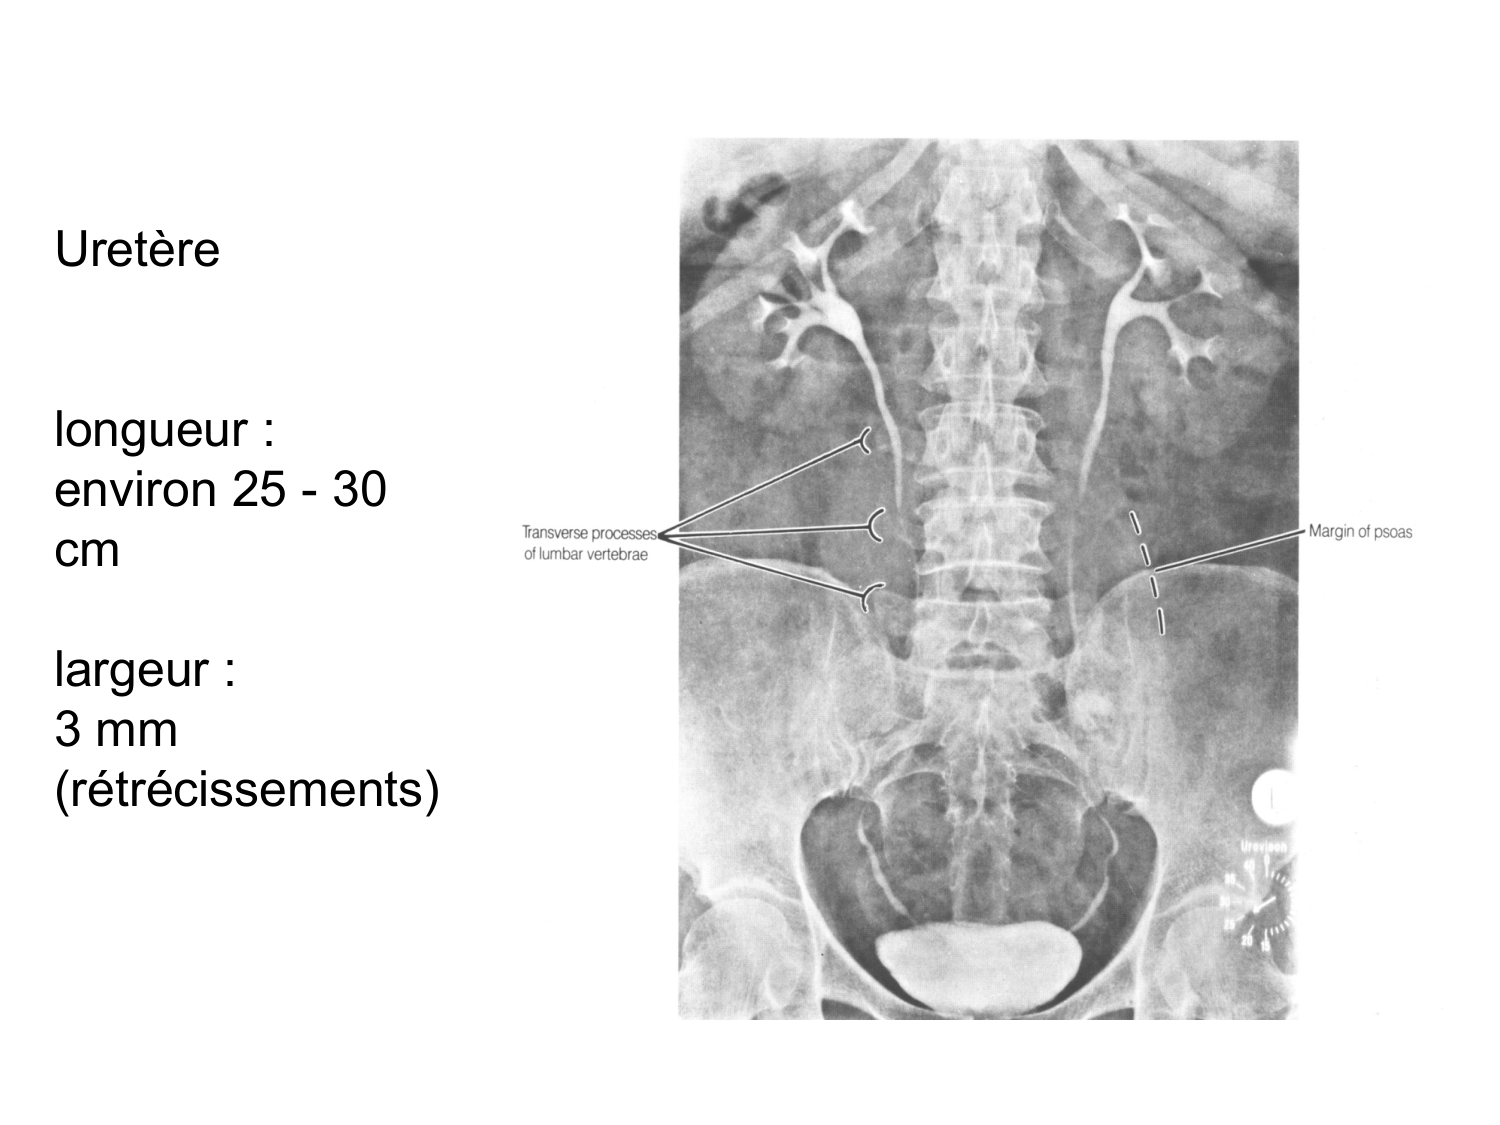

11.47 · Rein, voies urinaires et retropéritoine

Rein, voies urinaires et retropéritoine